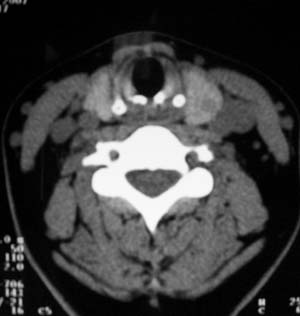

以下是引用zsl6918在2007-8-27 14:40:00的发言:[br]双侧甲状腺多发性低密度占位,边界清晰,密度欠均匀,尤以左侧明显,与周围组织分解清,考虑多发性腺瘤可能性大,不除外结节性甲状腺肿

以下是引用liaizhi在2007-8-27 15:20:00的发言:[br]双侧甲状腺散在多个囊性第密度影,左侧最大一个病灶与正常甲状腺分界尚可,气管受压稍右移。考虑甲状腺瘤的可能性大。

以下是引用zsl6918在2007-8-27 14:40:00的发言:[br]双侧甲状腺多发性低密度占位,边界清晰,密度欠均匀,尤以左侧明显,与周围组织分解清,考虑多发性腺瘤可能性大